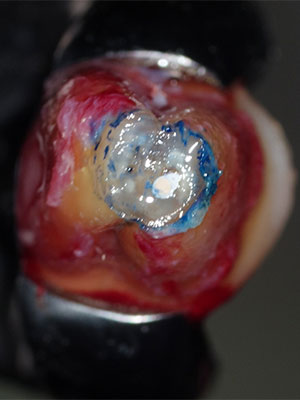

当院では、歯科専用の顕微鏡「マイクロスコープ」や「高倍率ルーペ」で患部を見ながら治療します。特に、マイクロスコープは、患部を十数倍に拡大して見ることができます。狭くて複雑な根管内を処置するには、拡大視野による施術が欠かせません。

写真は、実際にマイクロスコープで見た患部の様子です。どれだけ精度の高い治療ができるか、おわかり頂けると思います。